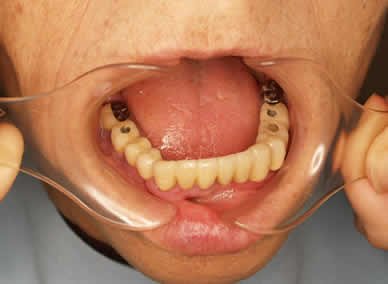

平成19 1010日  S17年生 男性

治療前

いままで上の入れ歯がどうしても合わない、粘膜が痛くなり医院を何度も替えてみたが上手くいかなかったそうです。この症例は良くみられるケースです。

本人の訴えは深刻で、最後にはあなたは特殊体質と言われたそうです。

インプラントも相談したが、骨の層が薄いので出来ないとのことでした。

私はこのケースを見てコーヌスで治療しました。咬む力を粘膜と残っている歯で支えればよい訳です。クラスプ義歯では噛む力が粘膜にくいこんで入れ歯が沈下し、歯肉を痛めてしまいます。

治療後